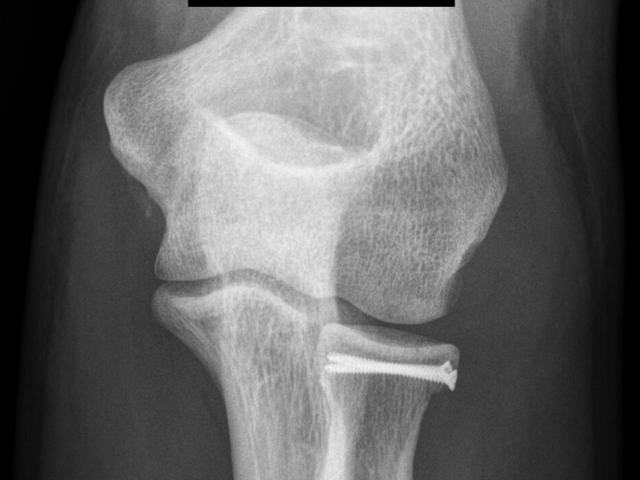

Síntesis de Cúpula radial: Las fracturas de la cúpula radial deben intentar ser reparadas para conservarla en su sitio y prevenir cualquier alteración de la función del codo o antebrazo, e incluso evitar dolor crónico en la muñeca. En ocasiones es necesario realizar síntesis o cirugía de reconstrucción de la cabeza radial como en esta imagen.

Fractura de cúpula radial: Fractura desplazada, visión lateral.